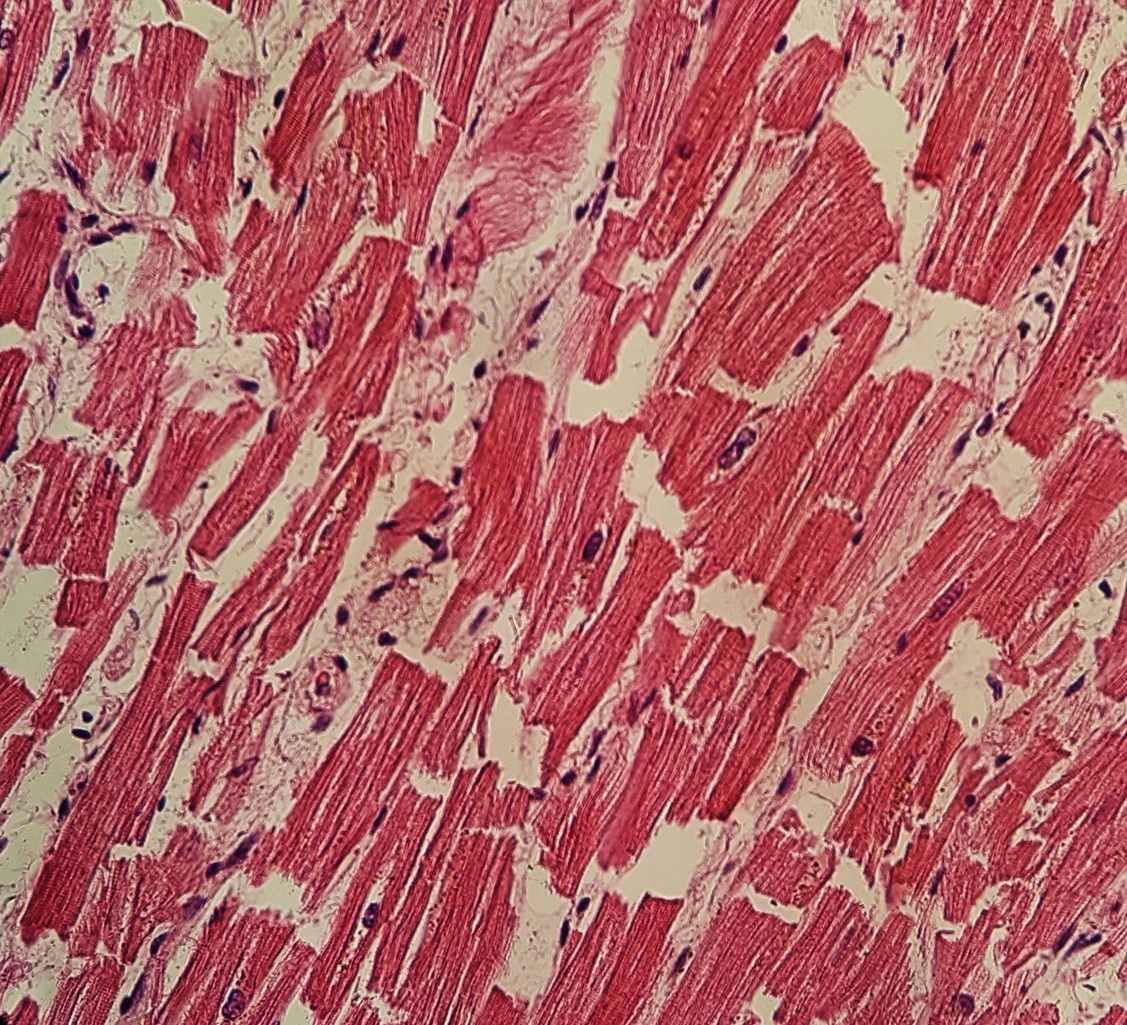

사이원반은 인접한 심근 세포를 연결하는 복잡한 구조이다. 부착판, 부착반점, 간극연접의 세 가지 세포 연접으로 구성되며, 이들은 area composita라는 단일 단위로 함께 작용한다. 사이원반 유전자 돌연변이는 심부전으로 이어질 수 있는 심근증의 원인이 될 수 있으며, 파열된 사이원반은 조직병리학적 관점에서 마이크로톰 사용 중 이상이나 강한 심근 수축으로 인해 발생할 수 있다. 강한 심근 수축은 과도하게 수축된 심근세포 다발의 대체, 네모꼴 심근세포 핵, 근세포분절과 분리된 신장된 심근세포 등의 징후로 나타난다.

사이원반은 인접한 심근 세포를 연결하는 복잡한 구조이다. 사이원반은 부착반점(desmosome), 부착판(fascia adherens), 간극연접의 세 가지 세포연접으로 구성된다.[8]

- 부착판은 액틴이 고정되는 부위이다.

- 부착반점은 중간섬유와 결합하여 심근 수축 시 세포가 분리되는 것을 방지한다.

- 간극연접은 인접 세포의 세포질을 전기적으로 연결하여 심장 활동전위가 퍼져나가게 한다.

이러한 세포연접들은 area composita라고 하는 단일 단위로 함께 작동한다.[11]